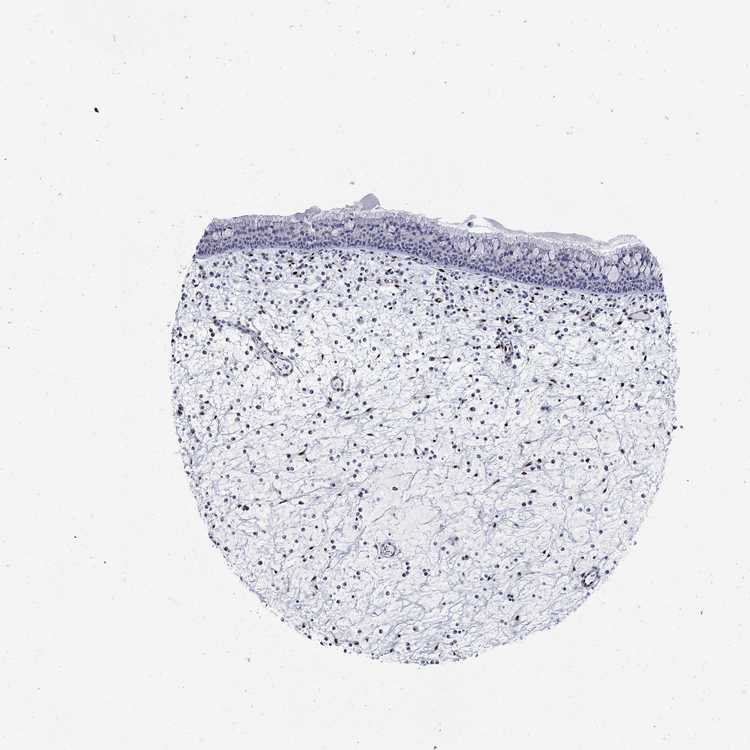

TISSUE PRIMARY DATA NASOPHARYNX Show tissue menu

Nasopharynx

NASOPHARYNX - Antibody stainingi

Antibody staining in the annotated cell types in the current human tissue is reported as not detected, low, medium, or high, based on conventional immunohistochemistry profiling in selected tissues. This score is based on the combination of the staining intensity and fraction of stained cells.

Each image is clickable and will lead to virtual microscopy that enables deeper exploration of all samples and also displays staining intensity scores, fraction scores and subcellular localization as well as patient and tissue information for each sample.

Antibody HPA027524Antibody CAB058686Antibody CAB079943

Respiratory epithelial cells Not detectedNot detectedLow